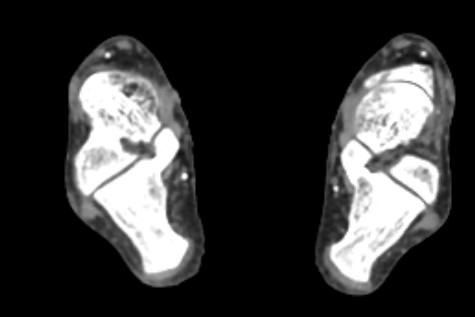

Основные показания для проведения КТ брюшного отдела аорты и артерий нижних конечностей могут включать:

• Стенозы и окклюзии: выявление и оценка степени сужения или блокировки артерий.

• Тромбозы: обнаружение тромбов и оценка их размера и локализации.

• Атеросклероз: определение степени и распространенности атеросклеротических изменений.